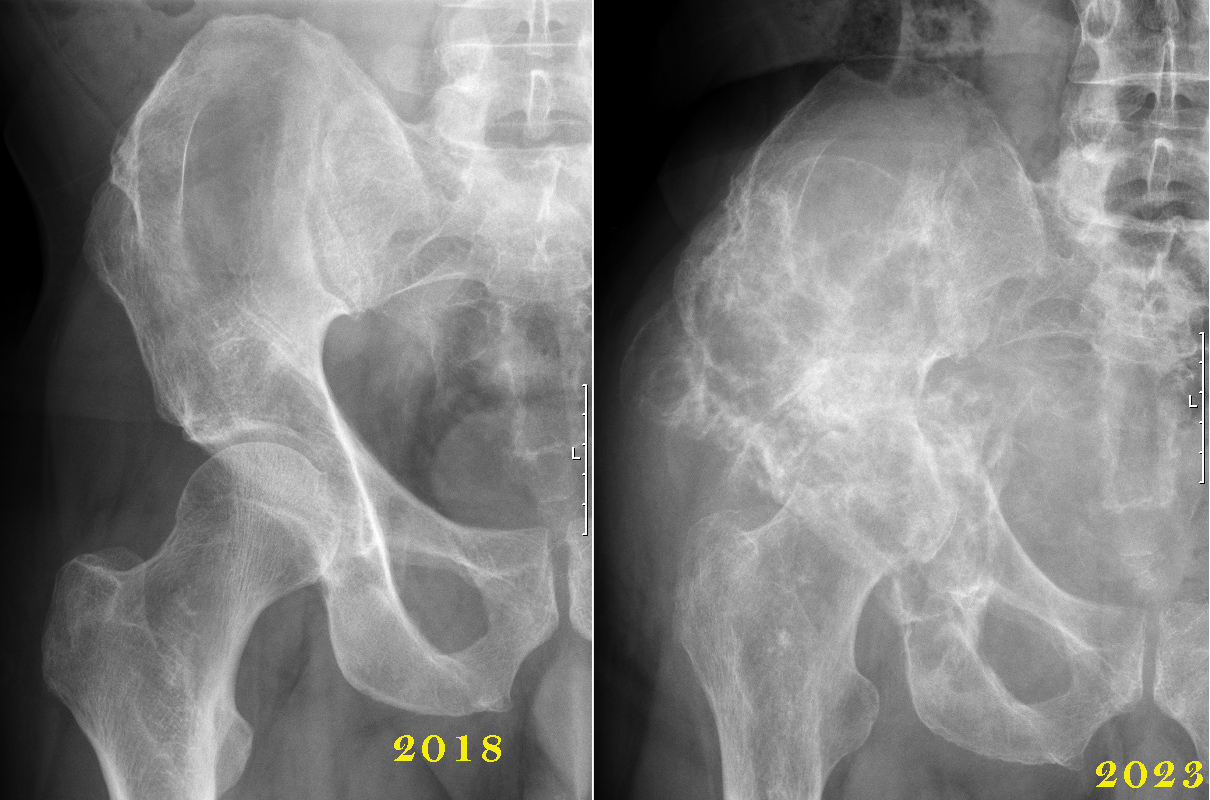

Becken rechts, Röntgen

| Inselspital Radiologie 19. 4. 2023 "CR SCHULTER LINKS IN AP/NEER VOM 19.04.2023 CR BECKEN IN AP UND HÜFTGELENK RECHTS AXIAL VOM 19.04.2023 Fragestellung/Indikation Klinische Angaben: Hüftschmerzen. Fragenstellung: Degenerative Veränderungen? Fraktur? Aktenanamnestisch Morbus Ollier. Befund Zum Vergleich dienen mehrere Voruntersuchungen, zuletzt die konventionellen Röntgenaufnahmen vom 10.04.2018. Schulter: Status nach Arthrodese des Schultergelenkes mit Rekonstruktion des proximalen Humerus und überbrückendem Osteosynthesematerial intakt, in regelrechter Stellung ohne Lockerungszeichen. Unveränderte Darstellung der ossären Strukturen des Scapula und des rekonstruierten Humerus. Miterfasst Lungenparenchym unauffällig. Clipmaterial auf Höhe des proximalen Humerusschaftdrittel. Deutlich osteopene Knochenmatrix. Keine wesentliche Befundänderung im Vergleich zur Voruntersuchung. Becken: Neu teils lytisch, teils sklerotische Raumforderung periacetabulär rechts mit Acetabulumfraktur, diese mit geringer Dislokation. Bei aktenanamnestisch Morbus Ollier der Befund in erster Linie vereinbar mit einem sekundären Chondrosarkom und pathologischer Acetabulumfraktur, DD allenfalls unbemerkt verlaufende nicht heilende Acetabulumfraktur mit ausgedehnter perifraktur-Ossifikationen/ Kalzifikation. Hüftgelenk links mit nur geringer Degeneration. Beurteilung • Schulter: unauffällige Verlaufskontrolle bei Status nach Sarkomresektion und Rekonstruktion. • Becken: Acetabulumfraktur rechts, in erster Linie pathologisch bei zu vermutendem Chondrosarkom bei M. Ollier." |

| Hirslanden Radiologie Bern, 24.4.2023, Raz, Ueli *06.01.1957 "MR und CT Becken sowie Rx Beckenübersicht vom 24.4.2023 Klinische Angaben, Fragestellung Morbus Ollier. Status nach sekundärem Sarkom der linken Schulter. 1. Diagnose 2002. Aktuell Befundprogress rechtes Os ilium DD: Sekundäres Chondrosarkom. Verlauf? Malignitätshinweise? Befund Die nachfolgenden Ausführungen beziehen sich sowohl auf die MRT, die Nativ-CT des Beckens wie auch die konventionelle Beckenübersicht. Die Beurteilung wird der Übersicht halber in 5 Sektoren aufgeteilt: Hemipelvis rechts, proximaler Femur rechts, Hemipelvis links, proximaler Femur links und das Sakrum. Hemipelvis rechts: Voraufnahmen zum Vergleich liegen aktuell im PACS nicht vor, der Patient hat auch keine Aufnahmen mitgebracht. Allerdings findet sich im PACS eine Beckenübersicht vom 10.4.18, wo im Os ilium rechts noch kein Enchondrom identifiziert werden konnte. Die nachfolgend beschriebene voluminöse polylobulierte Läsion mit Zentrum in der Fossa iliaca des Os ilium rechts zeigt in verschiedener Hinsicht eindeutige Hinweise auf eine maligne Entartung bzw. dürfte es sich bei der Läsion anhand der bildmorphologischen Kriterien und klinischen Angaben (Morbus Ollier) um ein Chondrosarkom handeln. Die entscheidenden Faktoren dieser Gewichtung liegen an der vollständigen Destruktion grosser Teile des Os iliums inklusive des Cortex, der erheblichen extraossären Weichteilausbreitung, der lokoregionären nachfolgend beschriebenen Weichteilinfiltrationen und den Periostreaktionen. Die Läsion ist polylobuliert und insgesamt etwas unregelmässig konfiguriert und zeigt auf dem axialen Bildmaterial Durchmesser von bis 17,5 x 12 cm und auf den koronaren Bildern Durchmesser von 15 x 9,5 cm. Sagittal misst man Durchmesser von 15,5 x 10 cm. Das konventionelle Übersichtsbild und dann vor allem die CT zeigt eine erhebliche ossäre Destruktion infolge Osteolysen, die in der Fossa iliaca ihr Zentrum haben und sich in alle Richtungen ausdehnen. Die Knochendestruktionen betreffen insbesondere auch den ossären Kortex. Die Osteolysen reichen bis in den vorderen acetabulären Pfeiler und erstrecken sich von hier in den vorderen Schambeinast rechts, wobei aber die parasymphysäre Region nicht betroffen ist. Weitreichende Osteolyse im dorsalen acetabulären Pfeiler und daran anschliessend im gesamten Os ischiadicum und auch am Übergang zum unteren Schambeinast - an dieser Lokalisation ist die Zusammenschau mit der MRT hilfreich, da die kleinen Lysen in der CT nicht so eindeutig sind. ln der MRT zeigt die Läsion die für die Tumormorphologie typische chondroide Hyperintensität in den fettsaturierten T2-gewichteten Sequenzen. Typische komplementäre Hypointensität in der T1-Gewichtung. Die polylobulierte konfigurierte mineralisierte chondroide Matrix des Tumors ist vor allem in der Peripherie gut zu erkennen. Diese zeigt und in der MRT ein hypointenses Signal und präsentiert sich wegen der hohen Dichte in der CT als lobulierte Verkalkung. Nach i.v.- Kontrastmittelapplikation wird eine grosse zentrale Nekrose der Läsionen sichtbar, die keine oder kaum Kontrastmittel aufnimmt; die vitalen Anteile der Läsion zeigen hingegen ein massives Enhancement. Die Weichteilausdehnung lässt sich hier am besten einschätzen (z.B. Serie 14). Es besteht ein relevante Tumorausdehnung sowohl nach aussen in Richtung Glutealmuskulatur wie auch nach innen in Richtung Pelvis. Von der Glutealmuskulatur betroffen bzw. infiltriert ist der Musculus gluteus medius und minimus; der Musculus glutaeus maximus dürrfte kaum betroffen. Aufgrund der Tumorausdehnung muss man von einer lnfiltration sämtlicher Muskelansätze und / oder Muskeln ausgehen, die am Os ilium ihren Ursprung haben. Mit eingeschlossen sind hier Crista iliaca, die Spina iliaca anterior superior und anterior inferior sowie das Os ischiadicum und der Übergang zum unteren und oberen Schambeinast rechts. Die Tumorausdehnung in Richtung Pelvis fülhrt zu einer breitbasigen Infiltration des Musculus iliacus. Der Musculus psoas anterior davon ist im Pelvis stark nach anterior verdrängt, ausgespannt und zeigt in der Übergangszone ein pathologisches Enhancement - man muss hier von einer zumindest punktuellen Infiltration ausgehen. Die Tumorausdehnung in Richtung Pelvis beansprucht volumenmässig fast die Hälfte des grossen Beckens und mindestens die Hälfte des kleinen Beckens. Die A. und V. iliaka communis und iliaca externa sind stark nach innen abgedrängt, erscheinen aber nicht infiltriert. Hingegen muss von einer Infiltration der Arteria iliaca interna rechts ausgegangen werden. Erhebliche Verdrängung der Harnblase zur linken Seite; das Organ scheint nicht infiltriert. Ebenso gilt dies für die Prostata, das Rektum und das Colon sigmoideum, das multiple Divertikel erkennen lässt. Proximaler Femur rechts: Das Caput femoris rechts ist zirkulär von Tumorgewebe umgeben; in diesem Sinne ist das Acetabulum inexistent. Dies hat auch dazu geführt, dass ein erheblicher Hochstand des Femurs rechts besteht infolge eines breitbasigen Einbruchs des Acetabulums, das mehr oder weniger vollständig lysiert ist. Der Hochstand gegenüber dem Femurkopf links beträgt über 2 cm. Computertomographisch findet sich im Caput femoris rechts eine umschriebene Osteolyse und zwar im apikoposterioren Anteil. An dieser Lokalisation ist in der MRT nach i.v.- Kontrastmittelapplikation ein signifikantes Enhancement zu erkennen. Diese Befundkonstellation ist höchst verdächtig auf eine Infiltration des Feinurkopfes. Daneben sind keine Osteolysen zu erkennen; das Caput und Collum femoris zeigt aber inhomogene Knochenmarksödeme die assoziiert sind mit einem inhomogenen Enhancement des Knochenmarks, das bis zur Regio intertrochanterica reicht. Entlang diesem Verlauf sind mehrere grobschollige Verkalkungsherde in der spongiösen Matrix zu erkennen. Anzufügen bleibt hier noch, dass das Beckenübärsichtsbild vom 10.04.18 keine Coxarthrose rechts oder links zeigte also - es höchst unwahrscheinlich oder ausgeschlossen ist dass diese Pathologien in Zusammenhang mit einer Arthrose stehen. Aufgrund der Gesamtpräsentation muss man meiner Sicht nach von einer lnfiltration des Femurkopfes ausgehen. Eine aseptische Osteonekrose erscheint als Differenzialdiagnose möglich aber unwahrscheinlich (Ausdehnung zu gross, keine subchondralen Einbrüche der Kompakta erkennbar). |